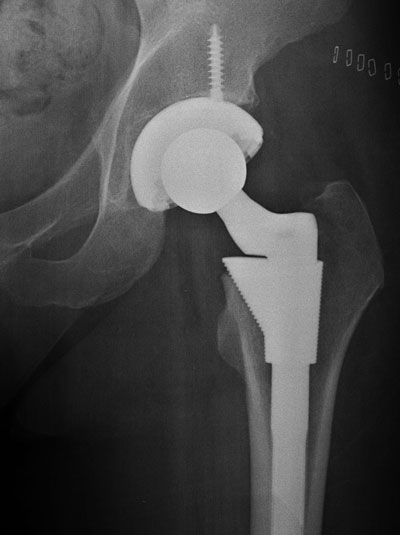

Hip replacement is a surgical procedure in which the hip joint is replaced by a prosthetic implant. Hip replacement surgery can be performed as a total replacement or a half replacement. Joint replacement orthopaedic surgery is generally conducted to relieve arthritis pain or in some hip fractures. A total hip replacement consists of replacing both the concave surface of the pelvis and the femoral head while half replacement generally only replaces the femoral head. Hip replacement is currently the most common orthopaedic operation.

Post surgery X Ray